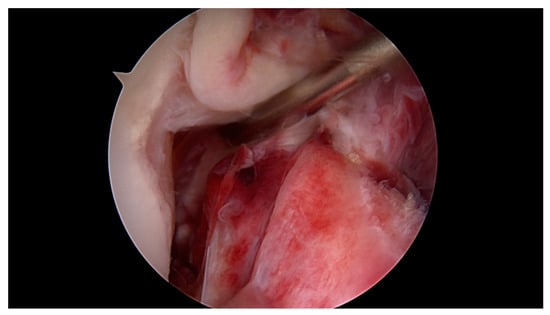

All surgeries were performed under spinal anaesthesia with the affected leg placed in an adjustable leg holder and with administration of an intravenous antibiotic prophylaxis. An examination under anaesthesia of the knee was performed prior to surgery in order to confirm ACL instability. The standard anterolateral and anteromedial portals were established to perform the arthroscopy to confirm all suspected findings with a probe. The ACL was assessed regarding tear pattern and tissue quality. When a proximal tear pattern with good tissue quality was identified (Figure 2), the patient was deemed eligible for arthroscopic ACL repair using SA: a labral scorpion suture passer (Arthrex, Naples, FL, USA) was used to pass a No. 2 FiberWire® (Arthrex, Naples, FL, USA) 3 times approximately 1 cm distal to the tear through the ACL remnant (Figure 3 and Figure 4). The femoral tunnel was drilled in anatomic manner within the footprint with 130 degrees knee flexion using a spade tip drill pin (Arthrex, Naples, FL, USA). An arthroscopic 45 degrees awl was used to perform a microfracture near the femoral footprint to enhance healing (Figure 5). Afterwards, a shuttling loop was passed through the femoral tunnel. The tibial drilling guide (Smith and Nephew, Andover, MA, USA) was placed at the anterior centre of the tibial footprint and a small skin incision at the anteromedial aspect of the proximal tibia was established to allow drilling and shuttling of a loop through the tibial tunnel. The tibial and femoral shuttling loop as well as the FiberWire® suture were retrieved through the anteromedial portal, the latter two placed in the tibial shuttling loop and passed through the tibial tunnel. Using the femoral shuttling loop, the SA construct containing a FiberTape® (Arthrex, Naples, FL, USA) armed TightRope® (Arthrex, Naples, FL, USA) and the FiberWire® were carefully shuttled through tibia and femur so that the TightRope® button flipped at the femoral cortex. The FiberTape® was fixed distally at the anteromedial tibia with a 4.75 SwiveLock® (Arthrex, Naples, FL, USA) with the knee in full extension. Subsequently, the FiberWire® suture and TightRope® tensioning suture were knotted on tension completing the ACL repair (Figure 6). Concomitant meniscal injuries were addressed either with direct repair (RapidLoc®, Mitek Products, Westwood, MA, USA) or with cautious partial resection when repair was deemed not feasible due to the configuration of the tear or pre-existing degenerative meniscopathy (Table 1). Concomitant chondral injuries were carefully smoothed or prudently underwent nano-fracture under direct vision.

Figure 4. Using the labral scorpion suture passer, a No. 2 FiberWire® is passed 3 times through the ACL remnant.